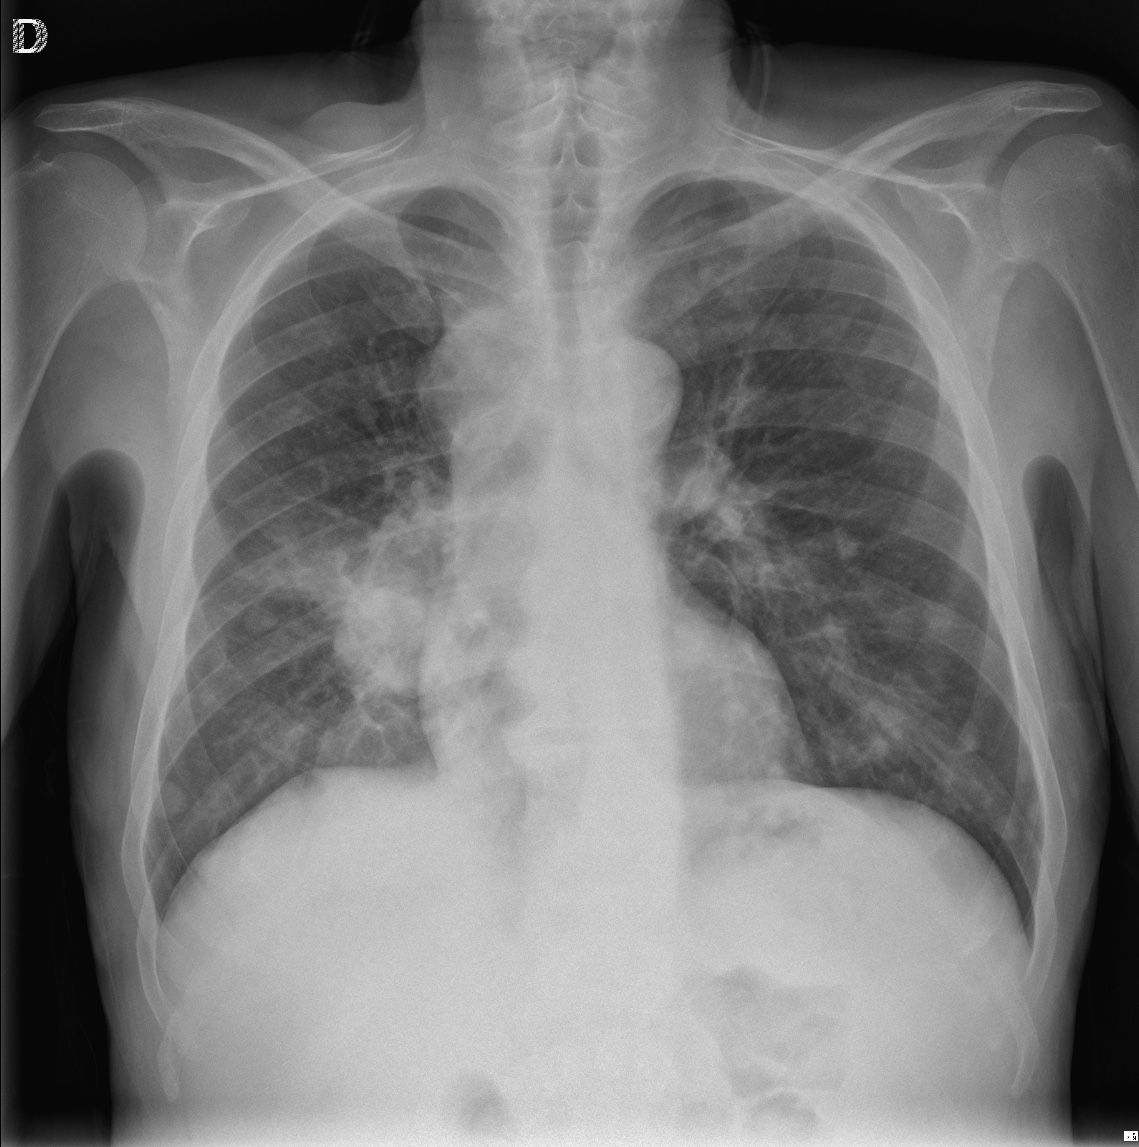

CASO: Febrícula y tos de 4 días de evolución.

Hallazgos:

- En la placa PA se observa una asimetría en los hilios pulmonares, el hilio izquierdo tiene una densidad aumentada.

- Tras examinar la placa lateral se observa un aumento de densidad en la columna que puede ser compatible con una condensación, es el signo de la desnificación vertebral.

SIGNO DE LA DENSIFICACIÓN VERTEBRAL: En la radiografía lateral normal, la densidad de la columna torácica tiende a disminuir desde la parte superior hasta el diafragma; la alteración de ese patrón por la presencia de una densidad superpuesta a la columna, indica la existencia de una consolidación pulmonar. Este signo adquiere especial valor cuando en la proyección posteroanterior la consolidación está oculta en el espacio retrocardíaco o en la base pulmonar.